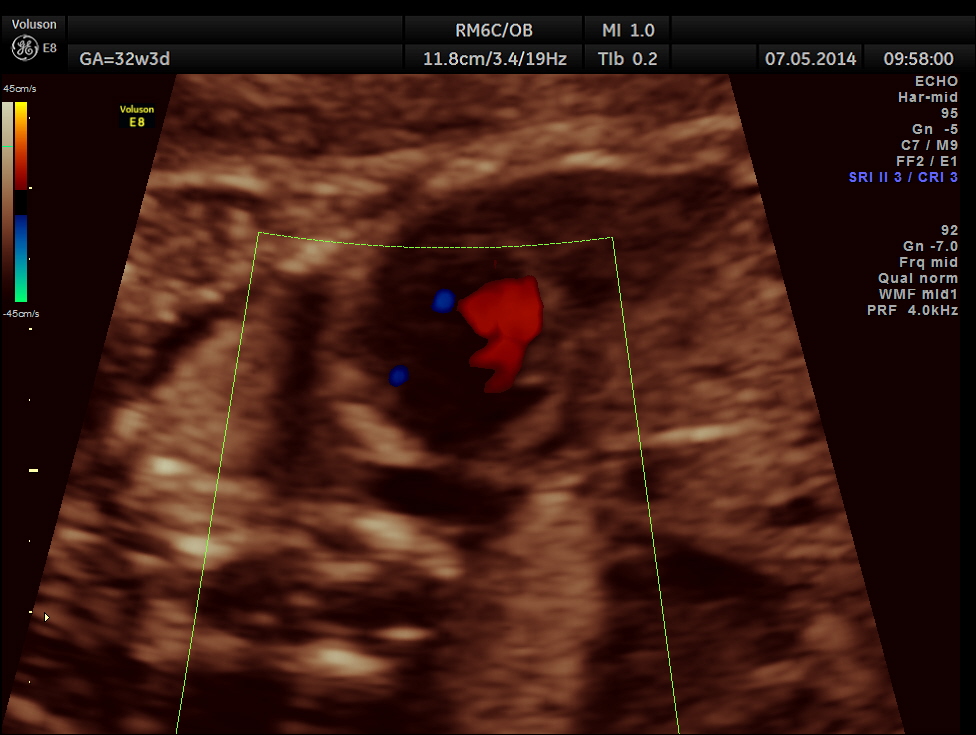

The following is a glass body imaging with a low flow setting. No pulmonary vein draining into LA could be made out.

A transverse vessel is seen below the left atrium and is not seen to drain into the left atrium.